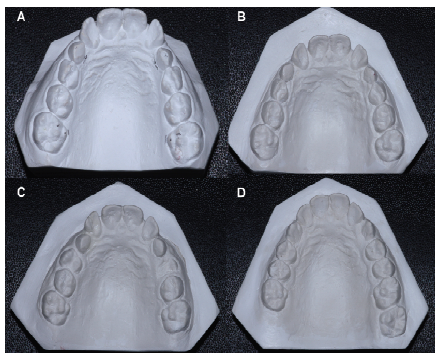

Dental casts and lateral cephalograms were obtained prior to RME (T0) as well as three months (T1), one year (T2) and three years (T3) after expansion (Figure 1). Lateral cephalograms were acquired from the same radiograph device (Ortholarix, Gendex, Italy). Cephalometric and dental cast measures at T0, T2 and T3 were compared to those of a control group (CG) made up of individuals with normal occlusion and similar ages to those in the EG. The same eligibility criteria were applied to the CG.

The following cephalometric measurements were evaluated: SNA, SNB, ANB, SN.GoGn, SN.PP, 1.PP and 1.PM (McNamara Jr., 1984) (Figure 2). The lateral cephalograms were scanned (HP Scanjet G4050, USA) and imported to a cephalometric analysis program (Cef X, CDT Softwares, Campo Grande, Brazil) (Figure 1). Intercanine and intermolar distances were measured on the plaster casts at T0, T1, T2 and T3 with the aid of a digital caliper (precision: 0.01 mm) (Mitutoyo-Japan). Four measures were made: A) gingival intermolar distance (union between palatal gingival margin and tooth); B) cusp intermolar distance (mesiopalatal cusps); C) gingival intercanine distance; and D) cusp intercanine distance (Lagravere, Major, Flores-Mir, & Orth, 2005) (Figure 3). The difference between the cusp and gingival measures allowed the determination of whether RME caused inclination of the teeth. One month after first measures, 50% of the lateral cephalograms and dental casts were randomly selected and the measures were repeated.